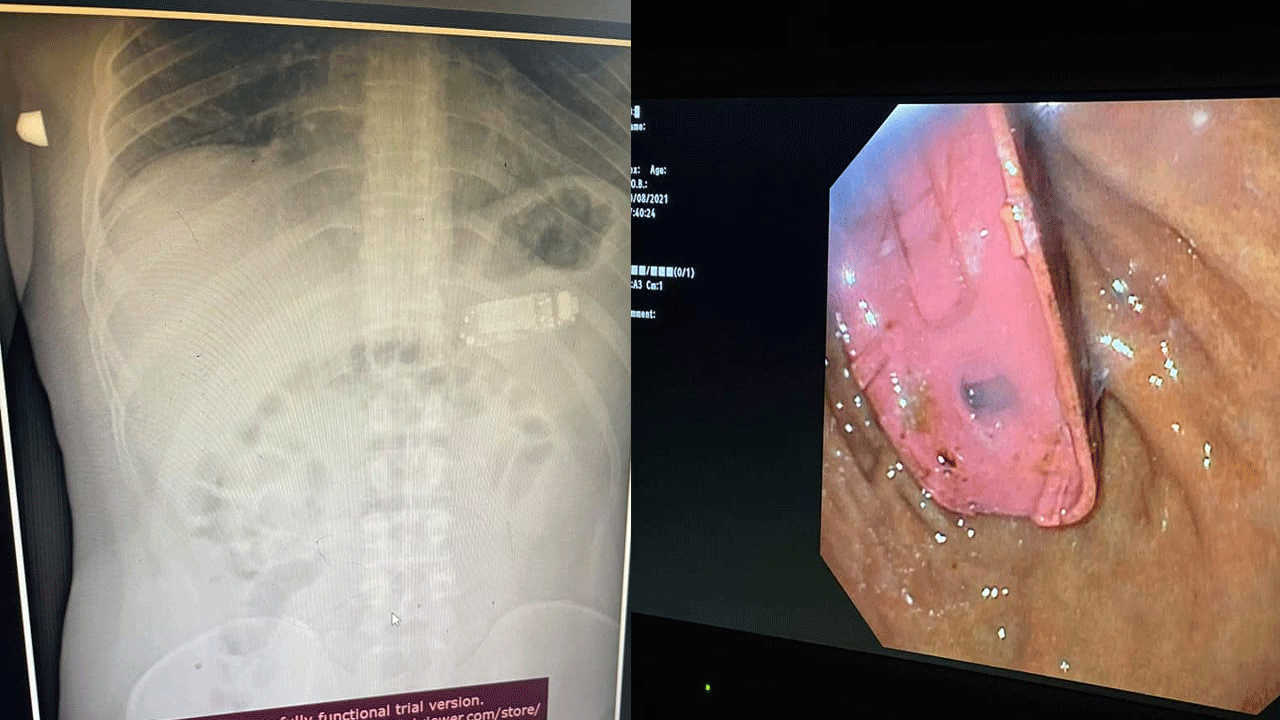

എന്നാൽ ശസ്ത്രക്രിയയിലൂടെ മൊബൈൽ പുറത്തെടുക്കുകയായിരുന്നു. ഡോക്ടർ ഫേസ്ബുക്കിൽ പങ്കുവെച്ച ചിത്രങ്ങളിലും എക്സറേയിലും എൻഡോസ്കോപ്പിയിലും വയറ്റിൽ ഫോണുള്ളത് വ്യക്തമാണ്.

ഫോൺ നീക്കം ചെയ്യുന്ന ശസ്ത്രക്രിയ ചിത്രീകരിച്ചിട്ടുണ്ട്. ഏത് ഫോണാണെന്ന് വ്യക്തമല്ലെങ്കിലും നോക്കിയ 3310 ആണ് വിഴുങ്ങിയതെന്ന് കരുതുന്നു.